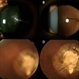

OPTOMAP - Description

- Fundus photograph of 43 year old male, hypertensive on medication, came for routine check up, and has been diagnosed to have poor vision left eye since childhood, denies any history of trauma. Vision left eye 6/18, Anterior segment normal, Fundus left eye shows excavated ,funnel-shaped optic nerve head, with central tuft of glial tissue obscuring the cup . The retinal vessels were seen emanating from the edge of disc in radial manner. In addition, the sectoral nasal retina shows localized area of hyperpigmented bony spicules like lesions. However, no history of nyctalopia or any other neurological disorder could be obtained.